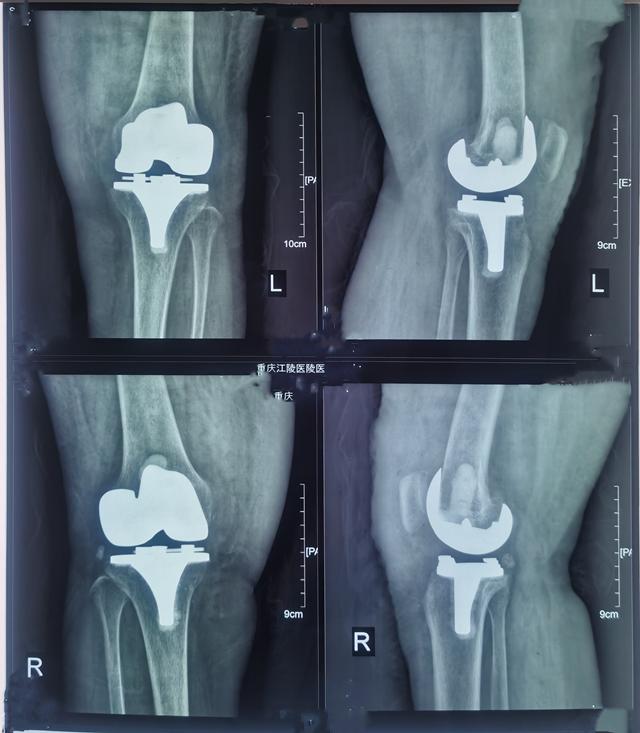

经过人工膝关节置换手术治疗,患者双侧膝关节症状明显缓解,术后第2天可逐步下床走动,第6天出院,出院时双侧膝关节疼痛减轻,双膝膝伸0度,屈85度,出院后需逐渐加强膝关节功能锻炼。

(术后检查)